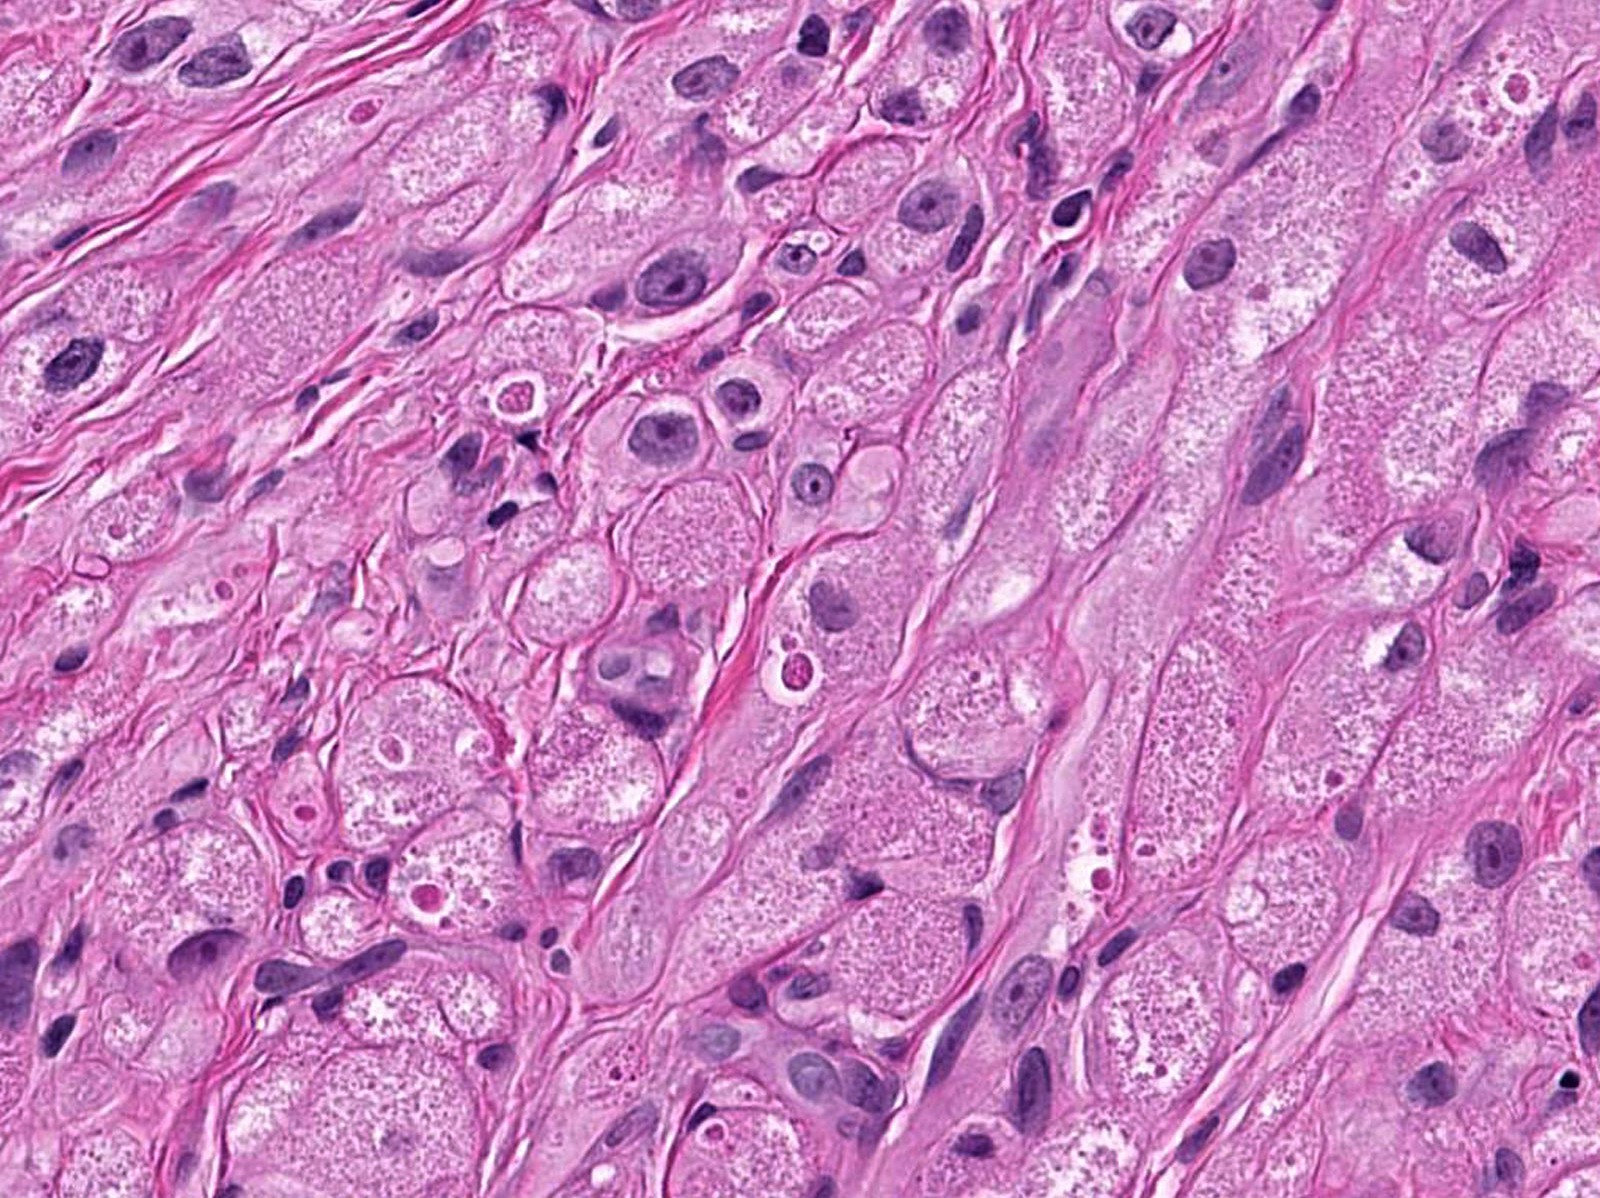

- Large polygonal cells with abundant eosinophilic granular cytoplasm and small, central nuclei

- Lysosomal macroinclusions (pustulo-ovoid bodies of Milian) are usually present (J Cutan Pathol 2007;34:405)

- Nonneural granular cell tumors (S100-) can exhibit nucleomegaly, pleomorphism and variable mitotic activity (Am J Surg Pathol 1991;15:48, Histopathology 2005;47:179)

Microscopic (histologic) images

Contributed by Jarish Cohen, M.D., Ph.D.